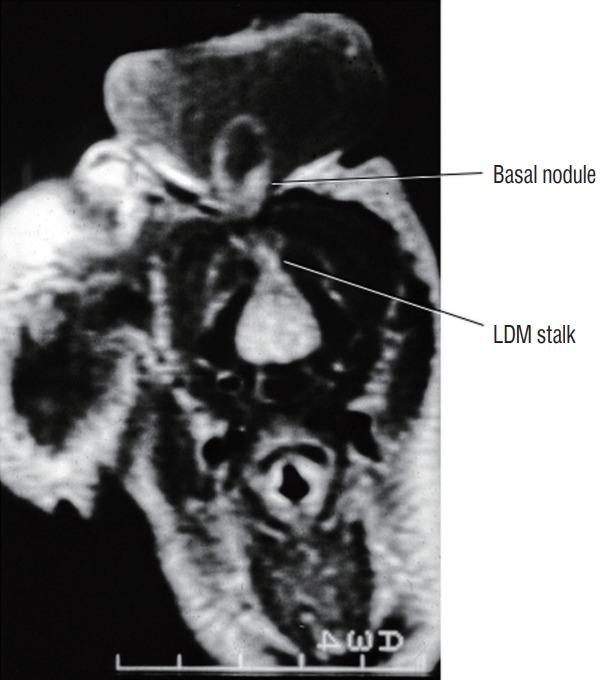

Spinal dysraphic lesions due to focal nondisjunction in primary neurulation are commonly encountered in paediatric neurosurgery, but the "fog-of-war" on these conditions was only gradually dispersed in the past 10 years by the works of the groups led by the senior author and Prof. Kyu-Chang Wang. It is now clear that limited dorsal myeloschisis and congenital spinal dermal sinus tract are conditions at the two ends of a spectrum; and mixed lesions of them with various configurations exist. This review article summarizes the current understanding of these conditions' embryogenetic mechanisms, pathological anatomy and clinical manifestations, and their management strategy and surgical techniques.

由于原发性神经管形成过程中的局灶性不分离导致的脊柱裂病变在小儿神经外科中很常见,但在过去10年中,由资深作者和王宇辰教授领导的团队的工作才逐渐驱散了这些病症上的“战争迷雾”。现在已经明确,有限性背侧脊髓裂和先天性脊柱皮样窦道是同一谱系两端的病症;并且存在各种形态的它们的混合病变。这篇综述文章总结了目前对这些病症的胚胎发生机制、病理解剖和临床表现,以及它们的治疗策略和手术技术的认识。